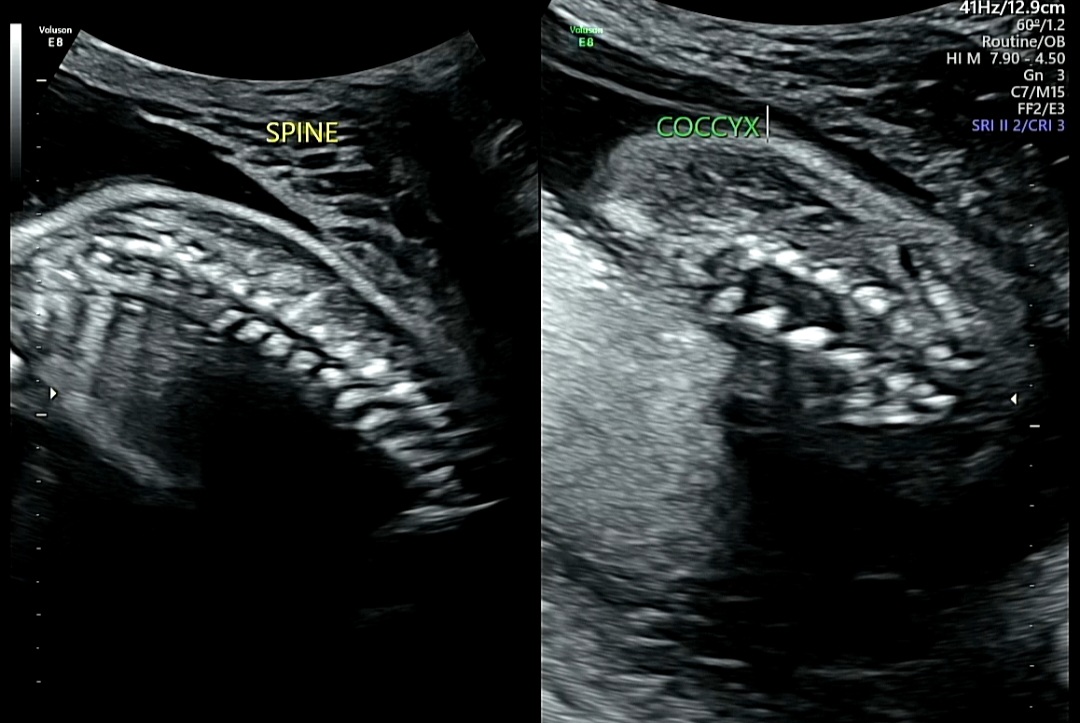

5. 척추 발달 확인

1) SPINE (척추)

SPINE: 척추, 아기의 등뼈 부분

→ 척추뼈가 곧게 연결되어 있는가

→ 틈이 벌어지거나(이분척추) 이상은 없는가

→ 척수관(신경이 지나는 통로)이 피부로 잘 덮여 있는가

즉, 신경관 결손(척추기형) 여부를 확인

2) COCCYX (꼬리뼈)

COCCYX: 꼬리뼈, 척추의 가장 끝부분

→ 척추가 엉덩이 쪽까지 정상적으로 이어지는지 확인

→ 척추 끝이 매끄럽게 마무리되어 있고, 피부층으로 덮여 있다면 정상